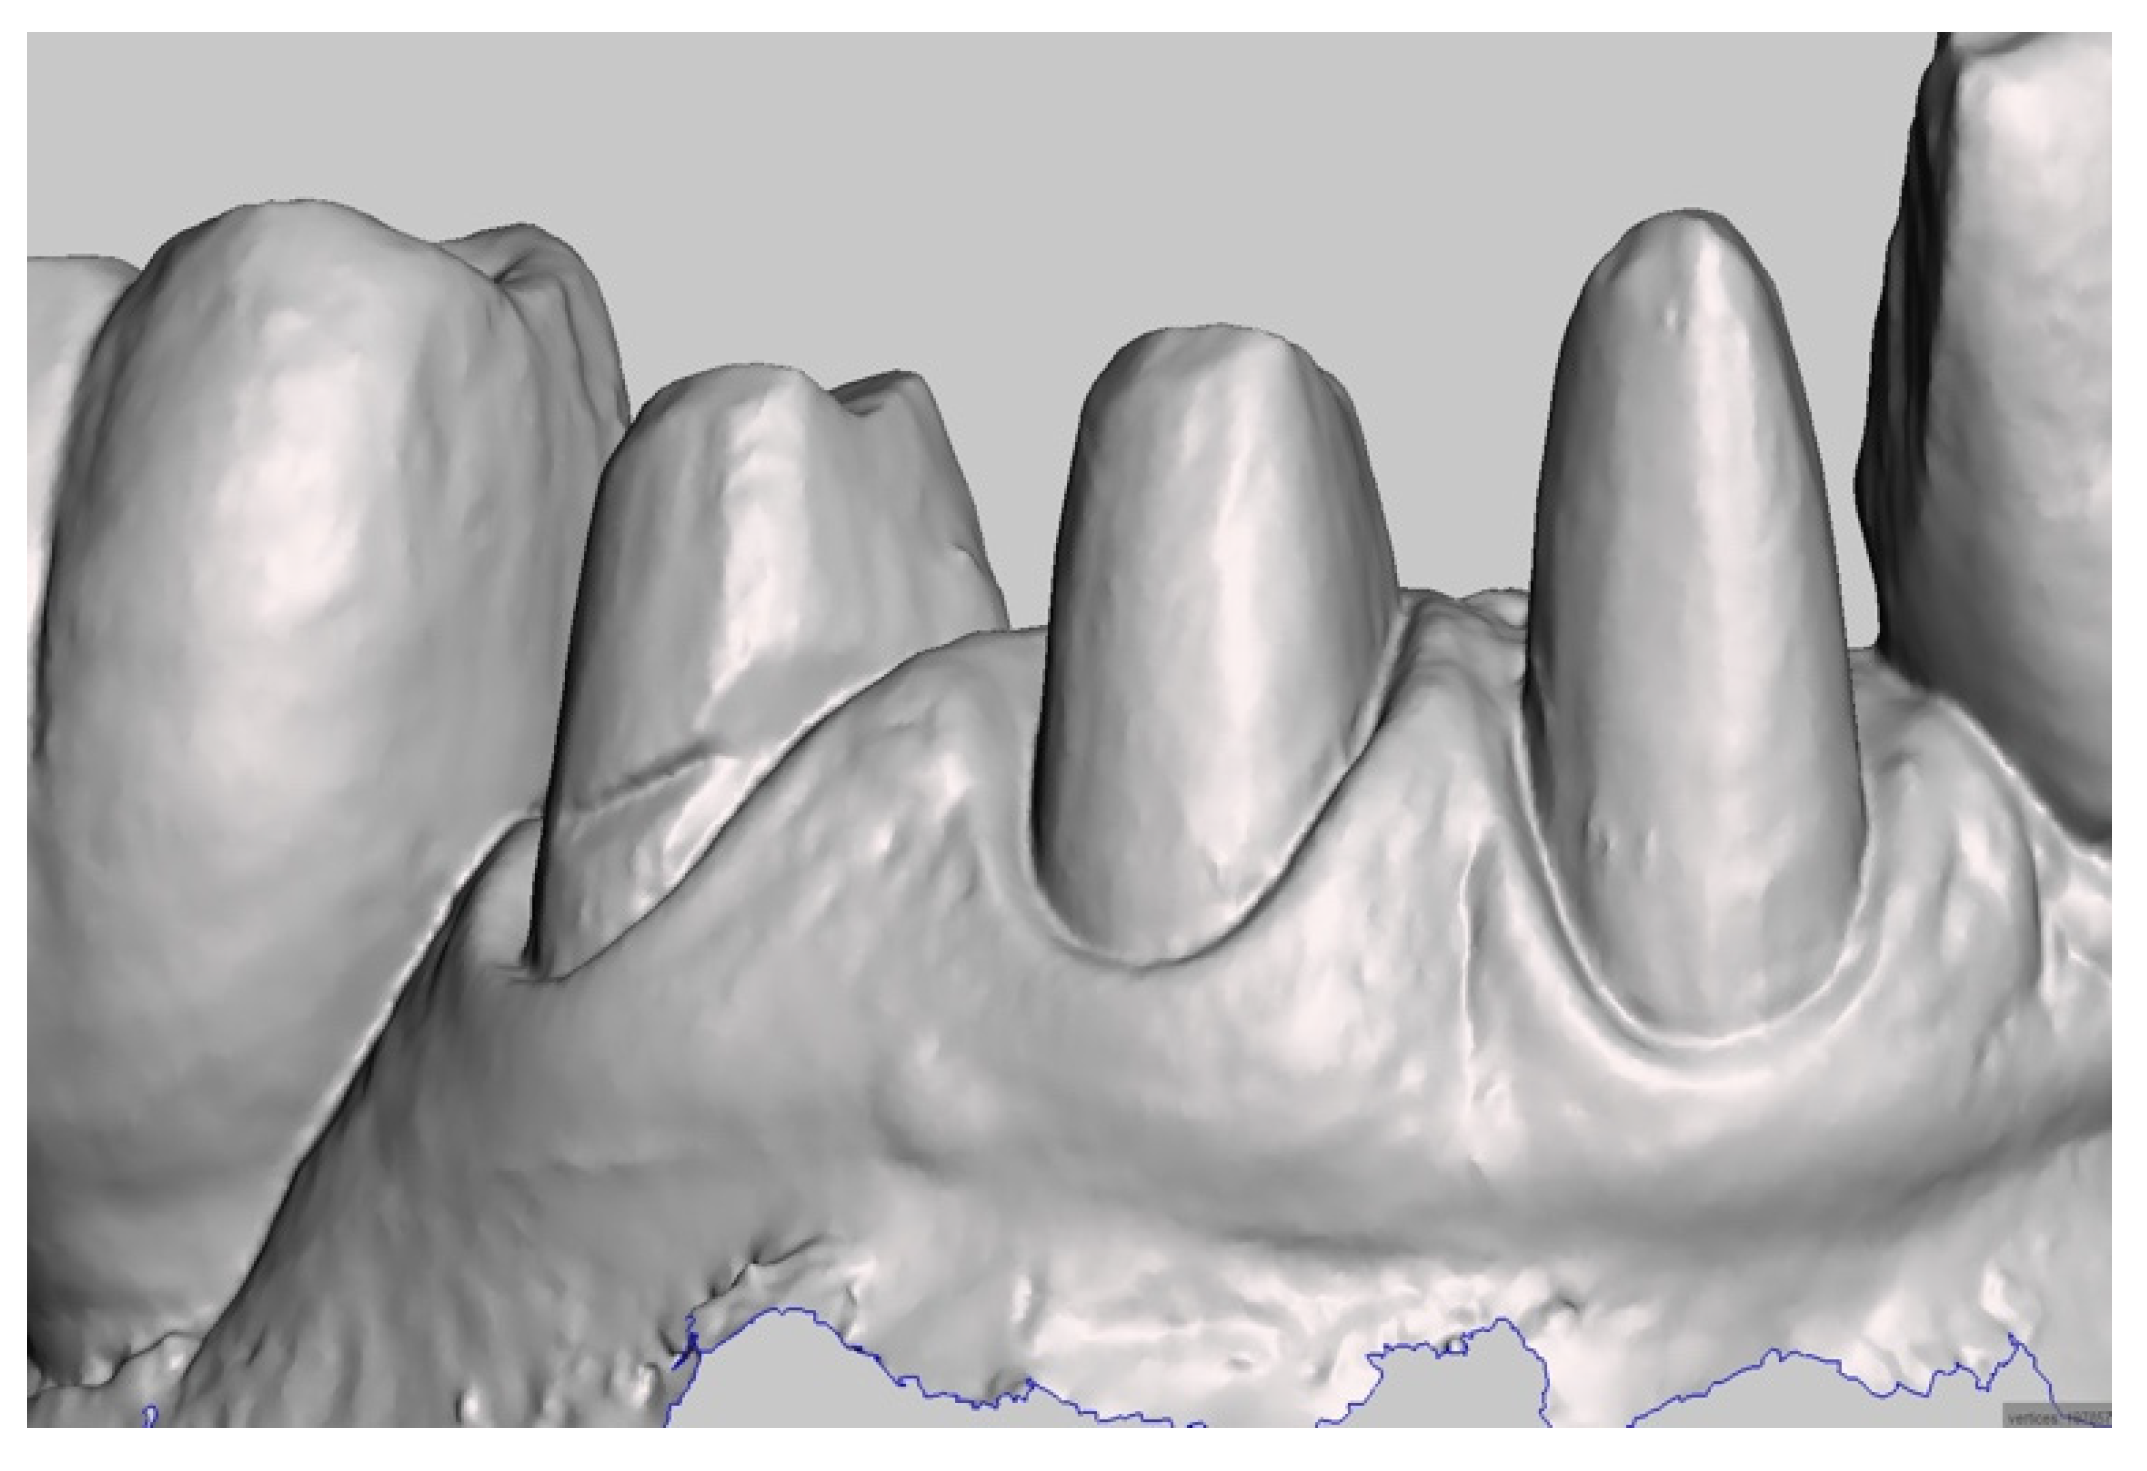

The master model was obtained by integrating two intraoral digital impressions (Figure 4), plus a scan of the temporary crowns using a Carestream CS3600 (Carestream Dental, Atlanta, GA, USA). The first impression scans the abutments, without retractor cords, following the recommended scanning protocol (both arches plus intercuspidal position). Next, an impression with the provisional restoration in place was taken. Subsequently, temporary crowns were scanned extraorally, acquiring their inner and outer margins (Figure 5). The resulting STL files were processed to produce a digital master model in which the data of the finish line of the abutments and of the surrounding tissues were derived from the temporary crowns. The workflow was performed using MeshMixer (Autodesk, Mill Valley, CA, USA) and Exocad (Align Technology, San Jose, CA, USA) (Figure 6).

Figure 4.

Digital impression of the abutments.